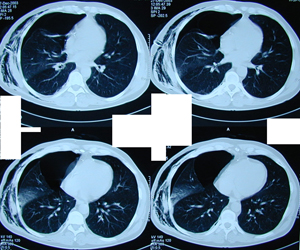

Εικόνα 3 α-ε

Αξονική τομογραφία του θώρακος. Διακρίνεται η παρουσία μεγάλου πνευμοθώρακος παρά την ύπαρξη της παροχέτευσης και την σύνδεση της συσκευής Bullau με συνεχή αρνητική πίεση. Επίσης υπάρχουν πολλαπλές μεγάλες εμφυσηματικές φυσαλίδες αμφοτερόπλευρα. Επιπλέον υπάρχει εκτεταμένο υποδόριο εμφύσημα.

Α-Β

Γ-Δ

Ε